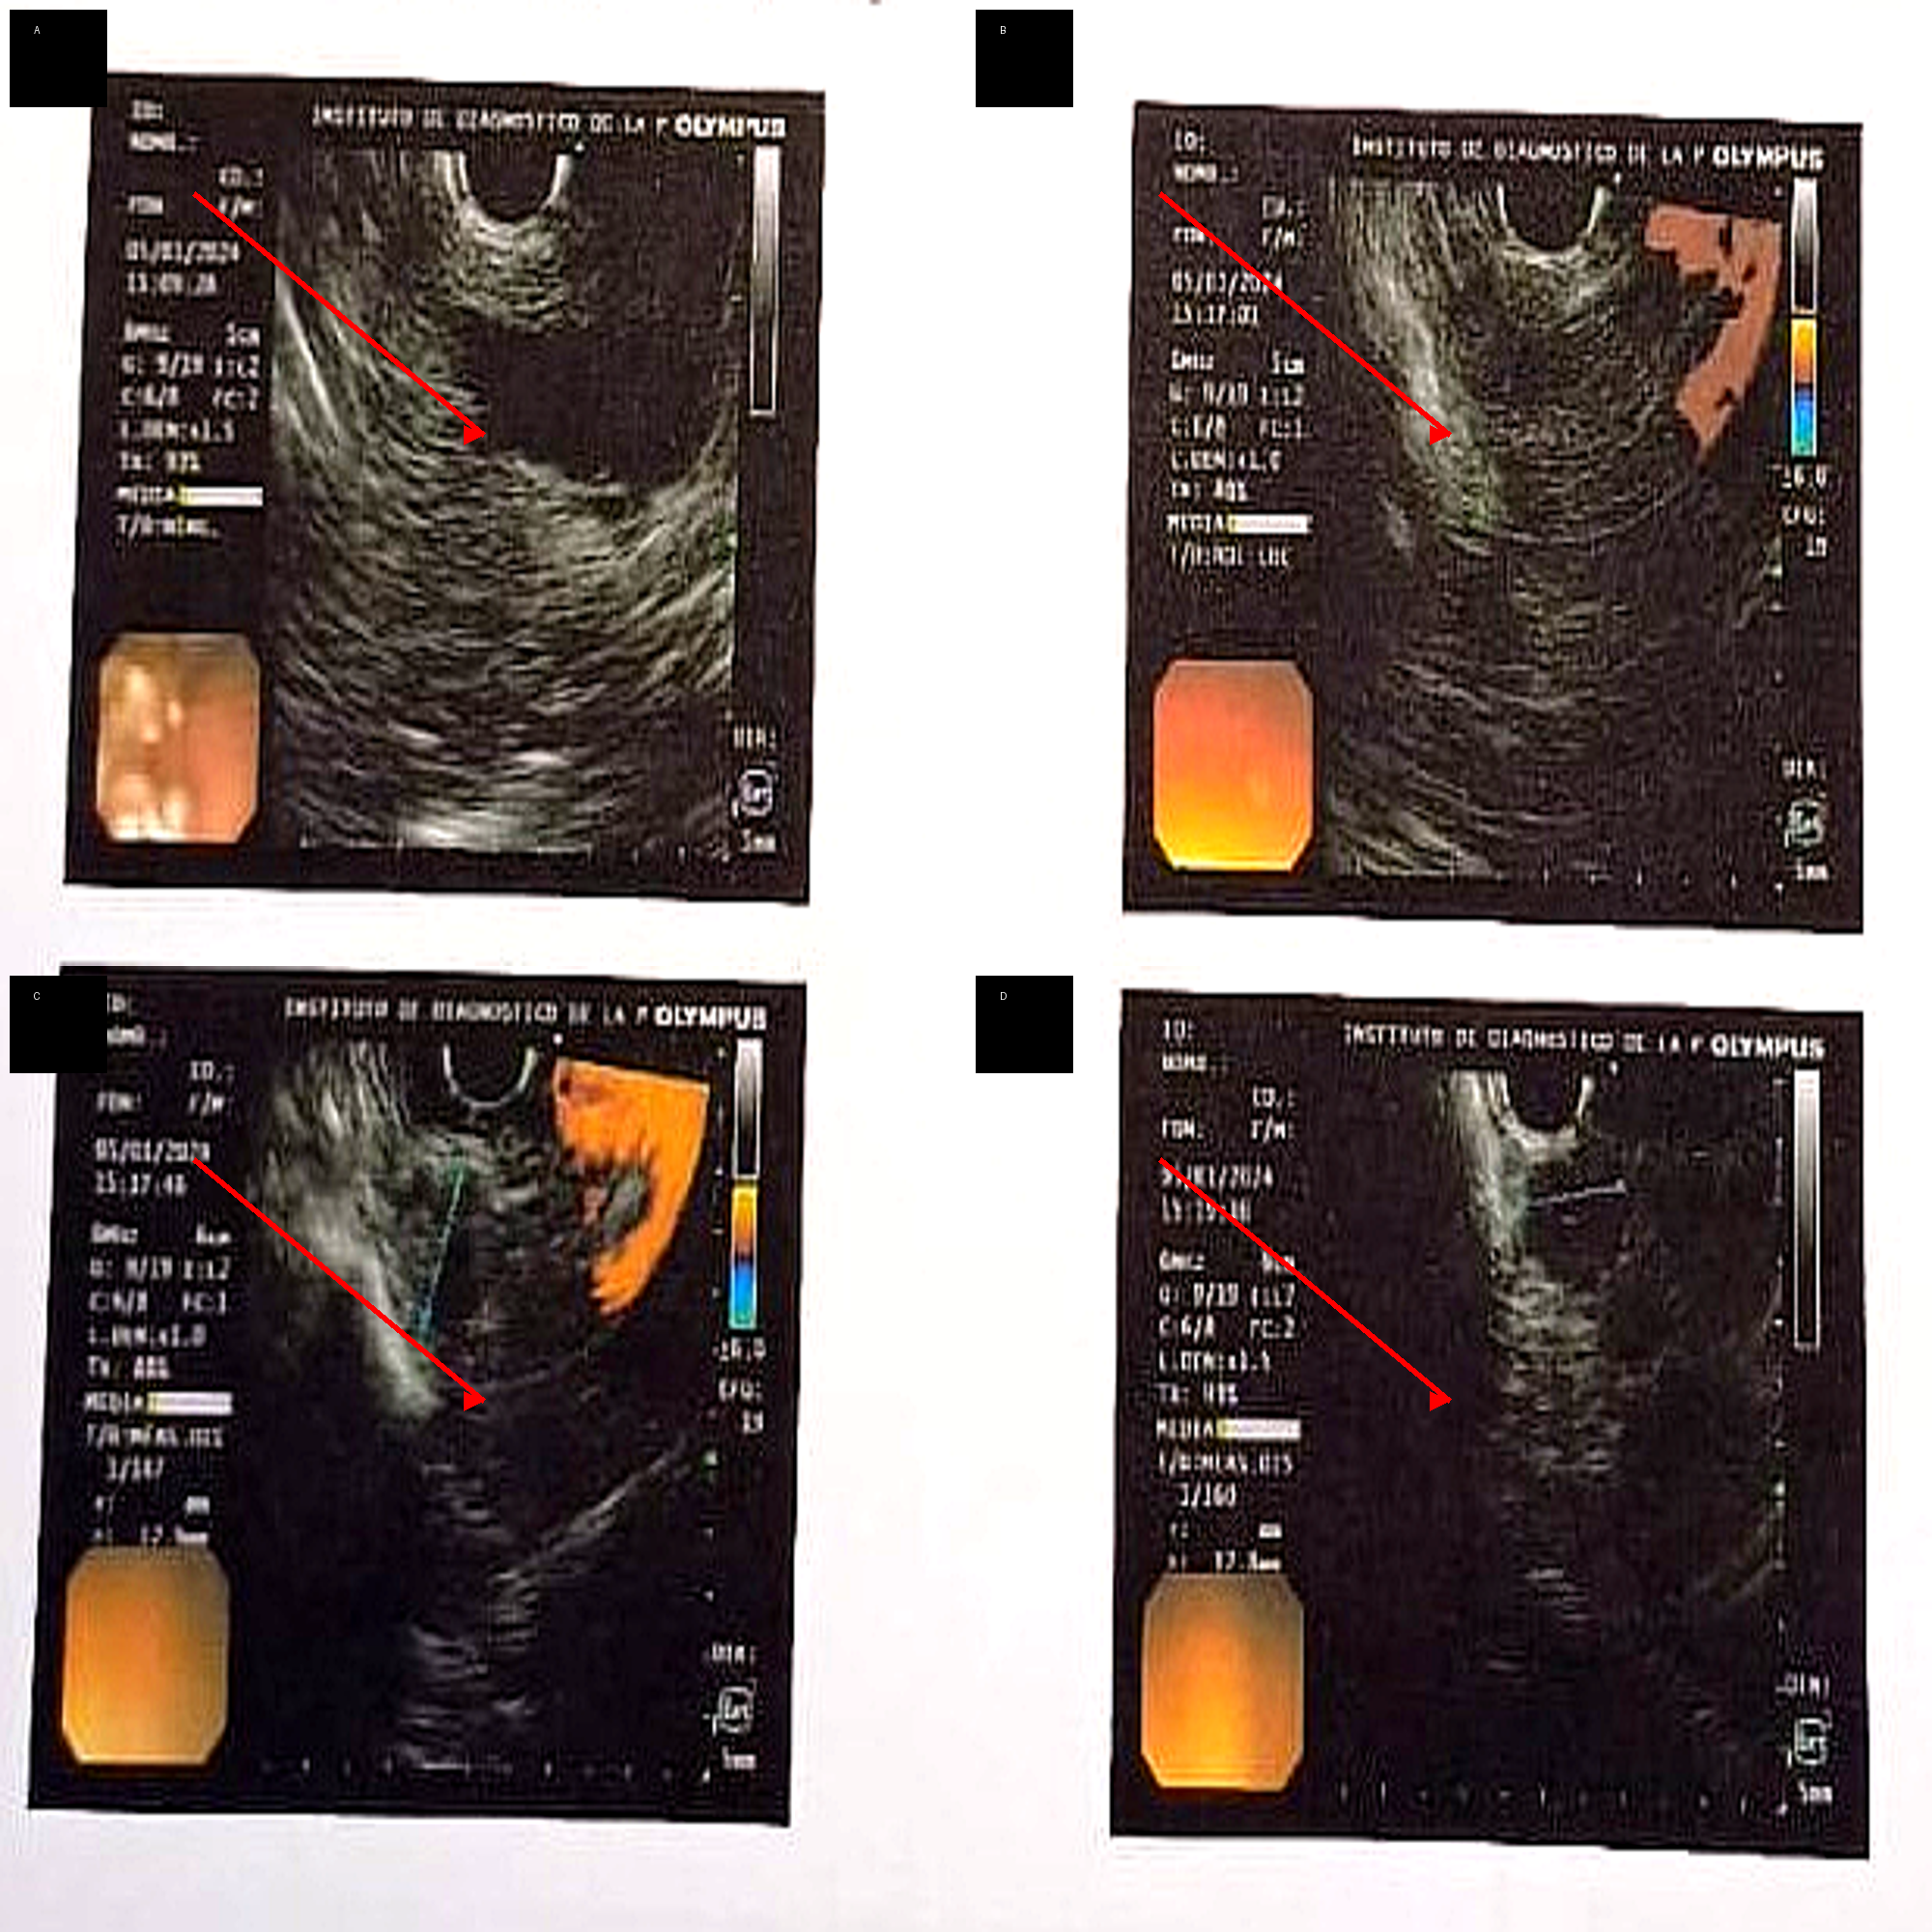

Figure 1: Endoscopic ultrasound (EUS) findings of pancreatic insulinoma located at the pancreatic neck.

(A–D) Hypoechoic, well-defined lesion (arrows) in the pancreatic neck, with internal vascularization on Doppler imaging and homogeneous echotexture.

EUS allowed precise localization and characterization of the lesion.

For tumor localization, computed tomography (CT), CT angiography, abdominal magnetic resonance imaging, and positron emission tomography (PET) with somatostatin analogs were performed, all of which were inconclusive. Subsequently, ^18F-DOPA PET revealed a focal area of increased uptake in the pancreatic head region. Endoscopic ultrasound (EUS) provided precise anatomical characterization, demonstrating a hypoechoic, round, well-defined lesion located in the pancreatic neck, measuring 13 × 12 mm (Fig. 1). EUS-guided fine-needle aspiration was performed, and cytological analysis revealed features consistent with a well-differentiated neuroendocrine tumor. Immunohistochemical evaluation showed a low proliferative index (Ki-67 <3%), consistent with a grade 1 tumor (Fig. 2).